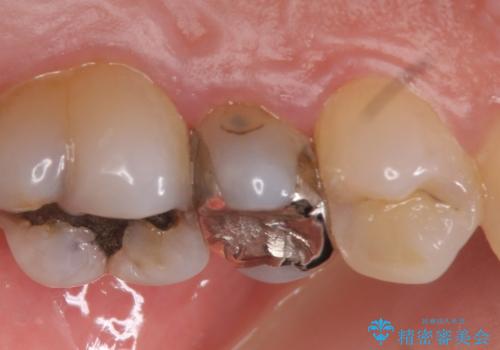

- 左上5番目の歯がしみるといらっしゃった方の症例です。

頬側の樹脂及び銀歯を除去後、オールセラミッククラウンにて補綴を行いました。